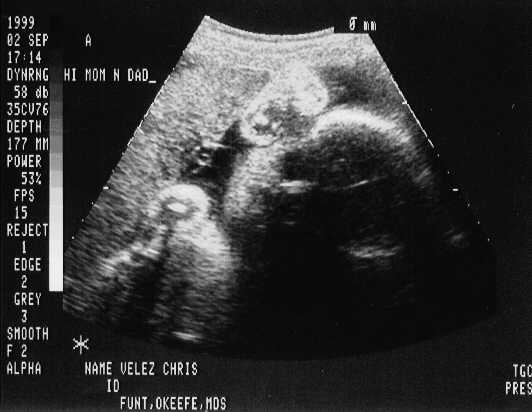

September 02, 1999 Sonograms

Kris is in her 33rd week. She can go in labor in 3 weeks!

Kristofer weighs 4.4 pounds.

The doctor says he can't believe how close they are in weight. They are almost NEVER this close in size.

Kristofer Henry

sono-0902-b1.JPG - 22.9 K